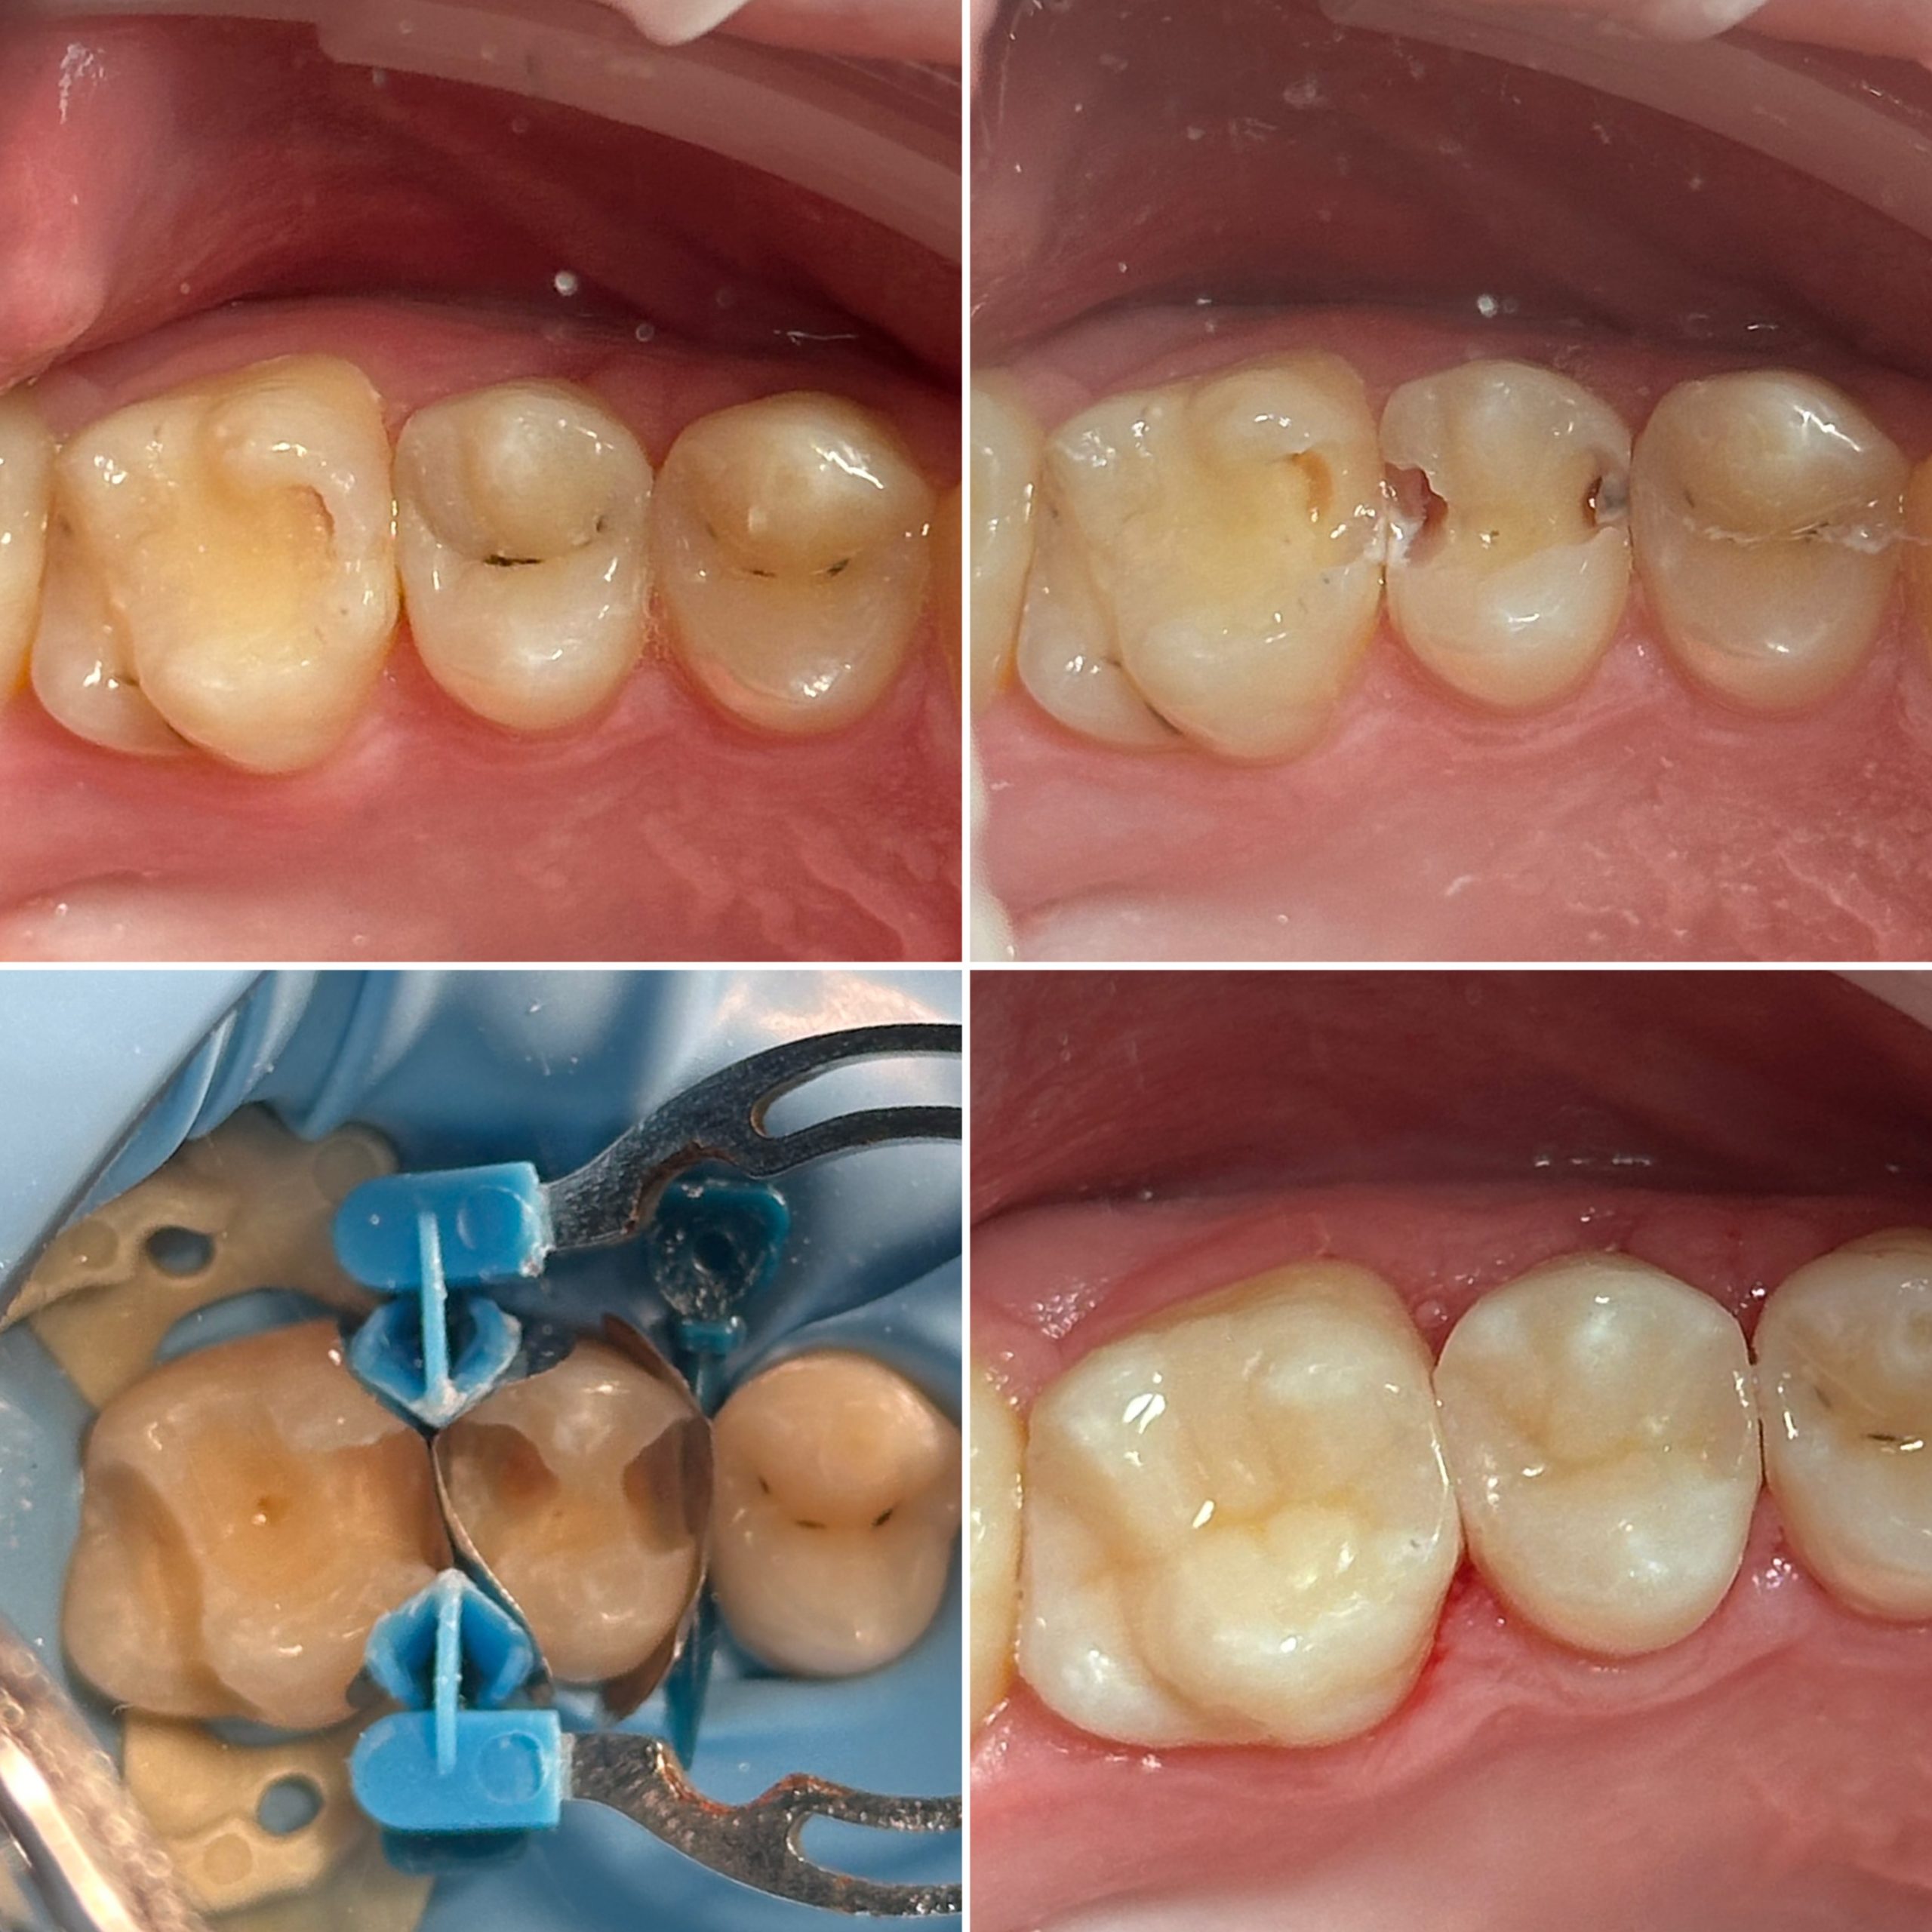

• Диагностика и лечение кариеса и его осложнений (пульпиты, периодонтиты)

• Художественная реставрация фронтального и бокового участка зубов

2022 год – «Прямая реставрация.Боковой сегмент.» Игорь Гудыма